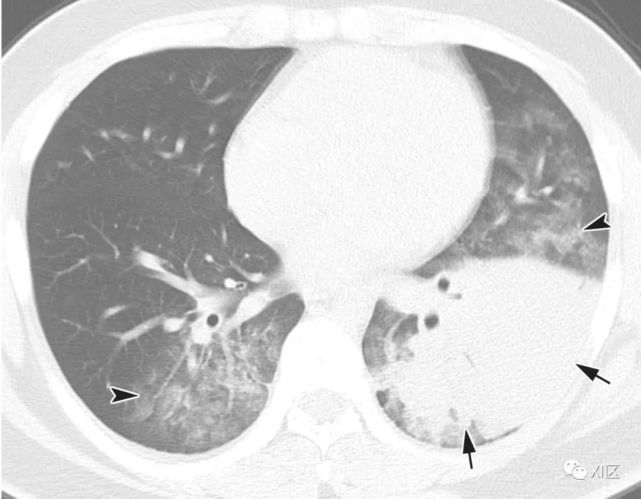

图4 水痘-带状疱疹病毒引起的肺炎显示多灶性1-10毫米清晰或不清楚的结节状阴影(箭),两肺周围有晕或斑片状GGO(箭头)。